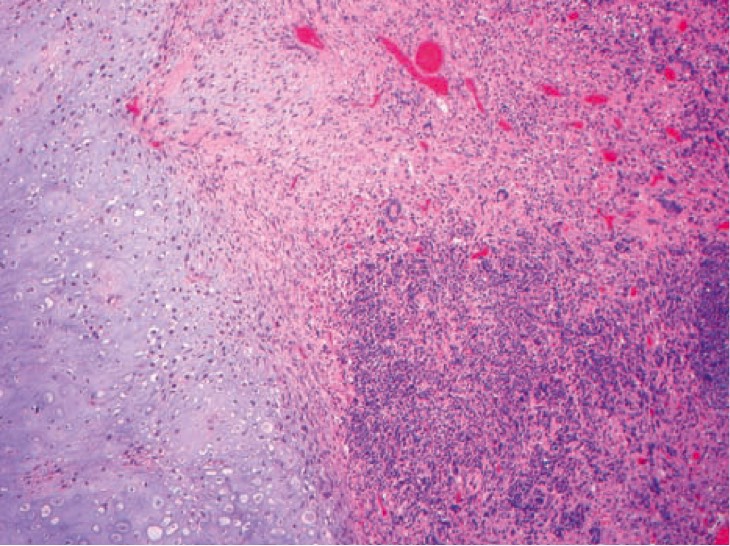

1050. В лобной доле 62-летнего пациента обнаружили